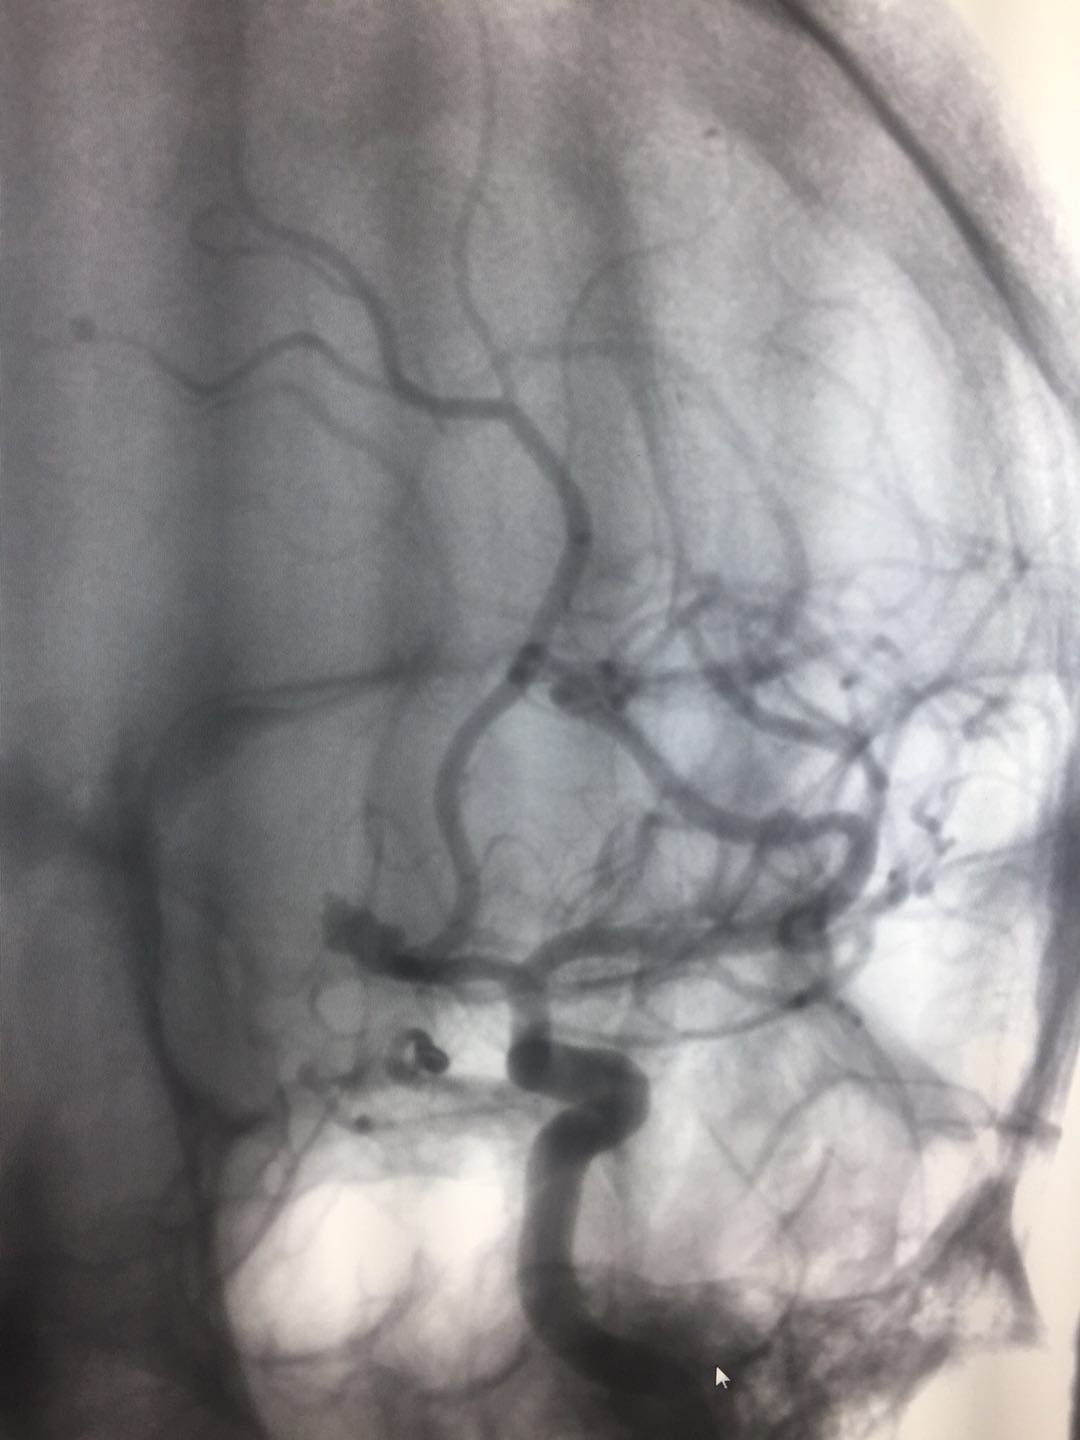

(术中)

在周兵熟练的操作及杨军团队良好的配合下,晚上7:30分,手术顺利完成,不仅出血等风险未发生,连支架都没用上——在弹簧圈阻塞瘤体与血管间通道效果不够好时,会植入支架帮助闭塞,但支架一旦植入,此后都需服用抗凝药物,而抗凝治疗与脑出血的止血治疗是矛盾的,患者术后的风险也将增加。